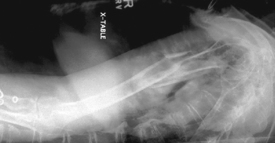

Transthoracic lateral (Lawrence method) (S)

Transthoracic lateral critique